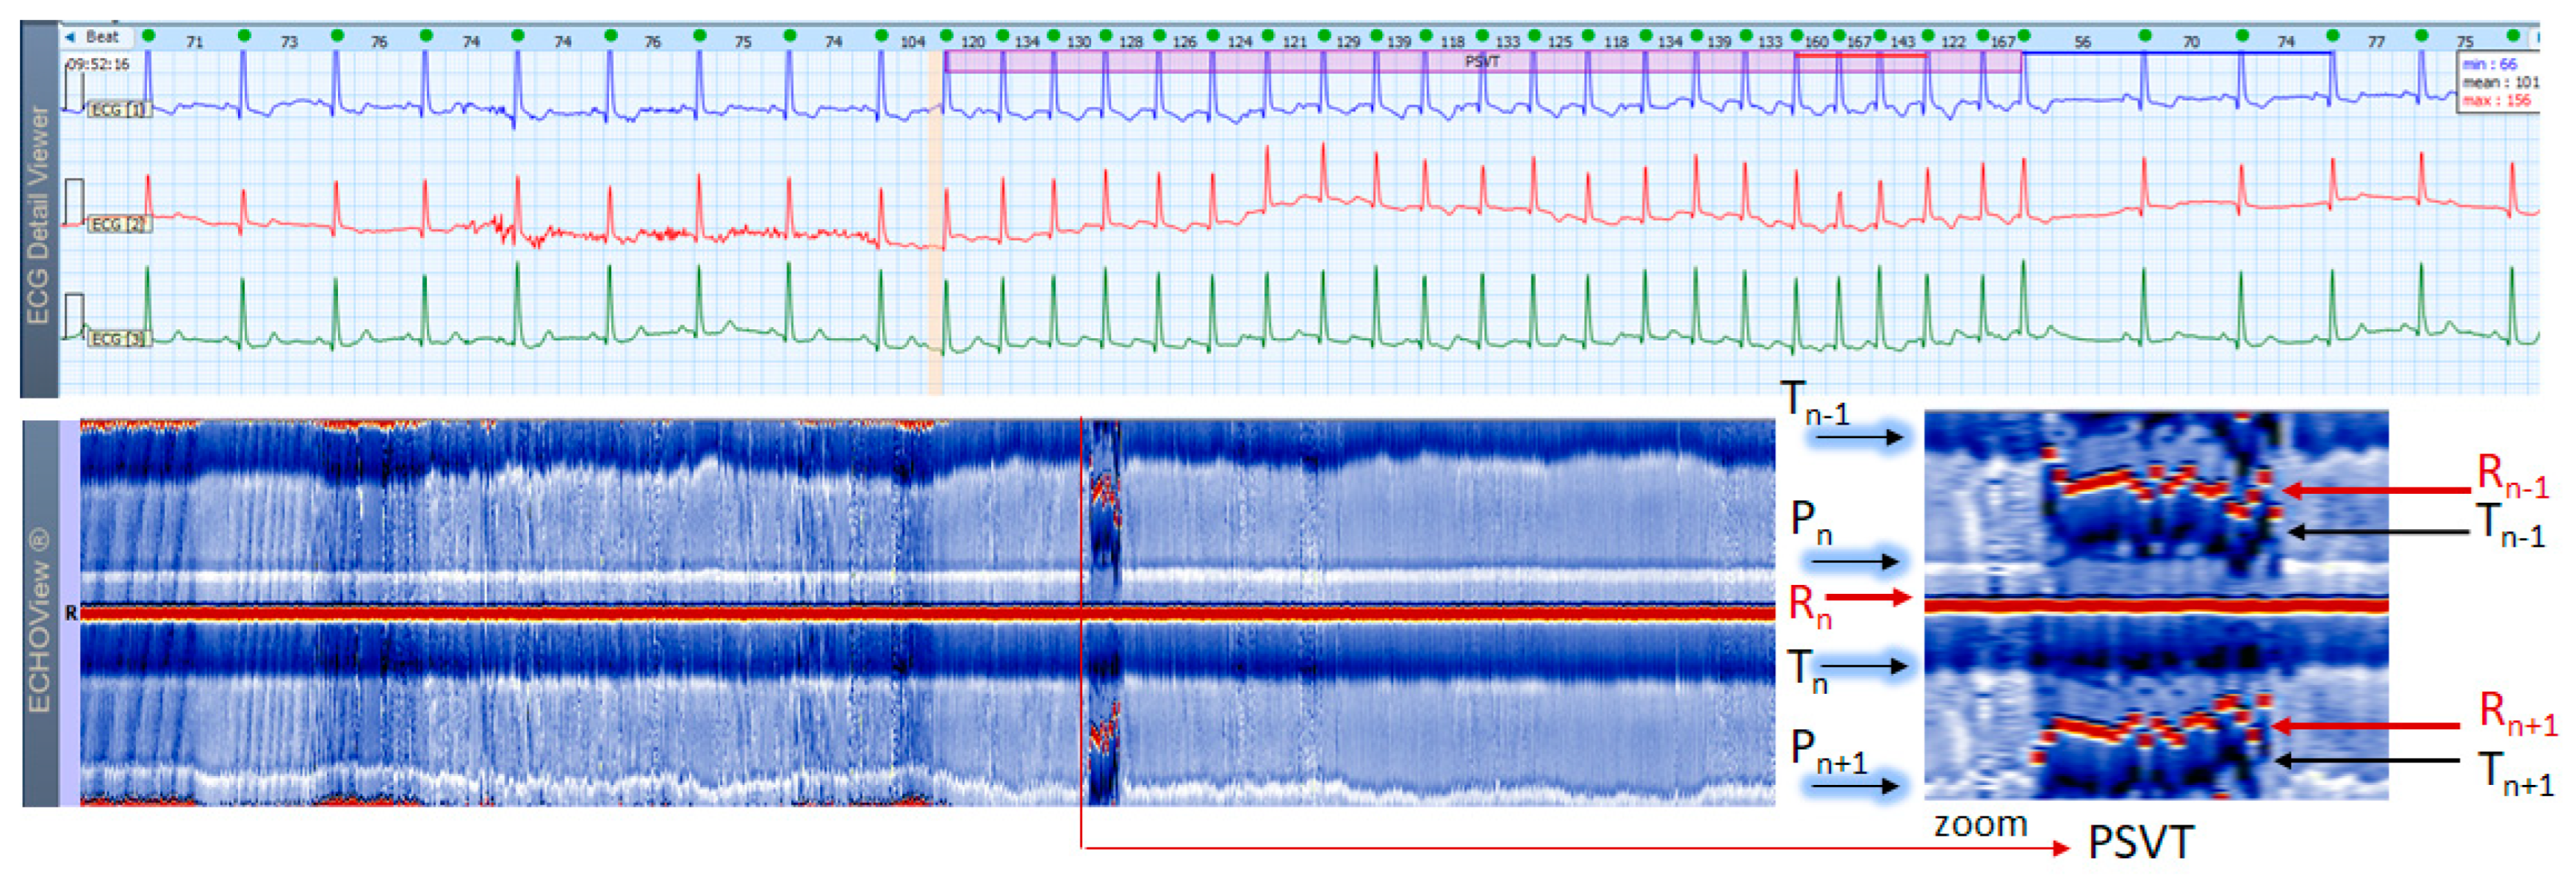

3.5. Paroxysmal Supraventricular Tachycardia Cases

This section interprets 3-lead Holter ECG strips and the corresponding ECHOView images (ECG lead 1) of three patients presenting short runs (≤10 s) of paroxysmal supraventricular tachycardia (PSVT) at the background of predominant NSR for most of the record (Figure 10, Figure 11 and Figure 12). These arrhythmias could occur at any age and are more common among women. The ‘slow-fast’ AVNRT is the most common form of PSVT, particularly in otherwise healthy hearts. It is caused by a reentrant circuit, created between two pathways (‘slowly’ and ‘fast’ conducting pathways) in or around the AV node. When the HR is too high, it is sometimes difficult to differentiate PSVT from high-rate SINT, especially in people without underlying cardiac or non-cardiac diseases. In patients with overt cardiac diseases or other pathological conditions (for example hyperthyroidism), PSVT must be differentiated not only from sinus tachycardia (common in such conditions) but also from high-rate AFL/AF. ECHOView color maps in such cases present quite distinctive patterns of PSVTs compared to NRS and SINT (Figure 6, Figure 7 and Figure 8). The beginning and the end of the arrhythmia can be identified at a glance (Figure 10, Figure 11 and Figure 12). In addition, ECHOView may facilitate the differentiation of the different PSVT subtypes. In summary, ECHOView improves the reading of Holter recordings with PSVT by saving time to visually locate the arrhythmia episodes and refine the diagnosis of these typically short events.

ECHOView interpretation turned out to be very important for some of our patients with episodes of supraventricular rhythm disorders such as SINT, SVT, AF and AFL. These arrhythmias are very common among the general population, affecting both younger and older people, with or without underlying cardiac injury [1,2,3,4,5,6,7]. A lot of non-cardiac conditions such as thyroid dysfunction, chronic lung diseases, electrolyte disturbances, infections (including COVID-19), etc. could also ‘unlock’ SVAs [1,2,8]. The diagnosis is based mostly on non-invasive ECG methods, mainly standard 12-lead ECG and 24–72 h Holter ECG monitoring [1,2,3,4,5,6,7,8,9,10]. Standard 12-lead ECG records are obtained in rest and their quality is usually much better than Holter ECG records, but conventional ECGs are not the ideal tool for diagnosing arrhythmias. They present time frames of about 10–20 s and many patients with SVAs could be missed because arrhythmias are often transitory [1,2,3,4,5,8]. For this reason, diagnosis is usually obtained by Holter ECG monitoring or event recorders [1,2,3]. However, most of these devices record less number of channels (1 to 3) in which P-waves of the normal sinus rhythm may not be demonstrated [1,2,3,4,5,6]. In addition, external factors such as movements, posture, skin contact of the electrodes, etc. may exert significant influence on the quality of the records and the morphology of ECG components, thus making the detection of P-waves even more difficult [1,8,17]. One of the most common ECG challenges is the differentiation of a high-rate sinus tachycardia from other SVTs (AVNRT, AVRT, focal AT) and sometimes from high-rate AF/AFL. Physical activities, emotions, panic attacks, pain/severe discomfort, febrility, etc. may cause expressed sinus tachycardia with complaints indistinguishable from a true tachyarrhythmia [3,5,9]. The ECG leads to shortening of the RR intervals, the impossibility of recognizing regularity/irregularity of the rhythm, and identifying/distinguishing the normal sinus P-wave from pathological P-waves of AT, F waves of AFL and f-waves of AF could make diagnosis uncertain, particularly if the patient has already had arrhythmias or risk factors for the development of them [5,7,9]. In this article we present several cases in which patient’s complaints and the Holter ECG records required differentiation between SINT, SVT and AF/AFL. In our cases, ECHOView facilitated the accurate diagnosis clearly disclosing the P-wave in SINT (Figure 6, Figure 7 and Figure 8) and the pathological atrial excitations in cases of true tachyarrhythmias SVT (Figure 10, Figure 11, Figure 12 and Figure 16), AF (Figure 13, Figure 14 and Figure 16) and AFL (Figure 15 and Figure 16) but also the contrastive ventricular pattern of NSVT. As the prognostic significance and therapeutic approach to arrhythmias can vary greatly [40], such as the need for oral anticoagulation in AF/AFL [1,2], the advanced perspective of ECHOView is an important tool to improve risk assessment and therapeutic decision-making.